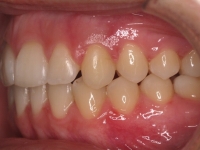

Clase II paciente 15 años

La paciente O.O. acude a nuestra consulta por:

– Canino 13 e incisivo lateral 42 en posición ectópica.

– Canino 23 incluido.

Con lo que decide realizarse un tratamiento de ortodoncia de duración de 24 meses con brackets damon Q.